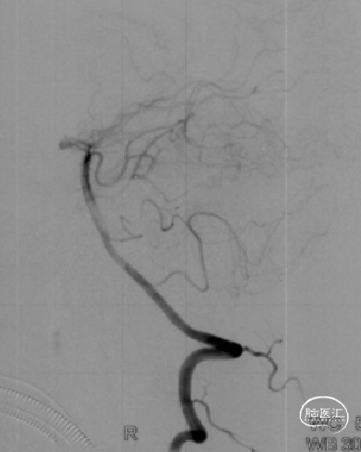

➤术前DSA检查

右侧大脑中动脉重度狭窄,左侧前循环未见明显异常。

病变部位: 右侧大脑中动脉M1段重度狭窄;狭窄率: 75.6%;狭窄长度: 6.10mm;参考远端血管直径: 1.27mm。

2022-07-27 术前正位

2022-07-27 术前侧位